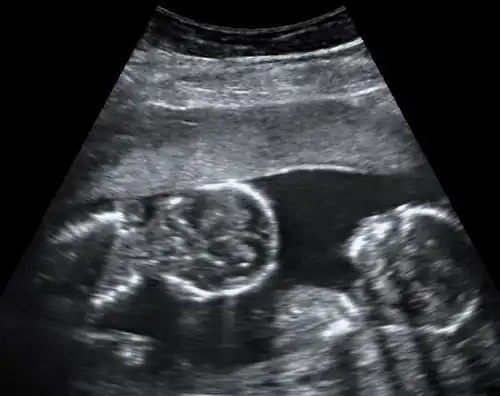

Abdominal ultrasonography of monoamniotic twins at a gestational age of 15 weeks. There is no sign of any membrane between the fetuses. A coronal plane is shown of the twin at left, and a sagittal plane of parts of the upper thorax and head is shown of the twin at right.